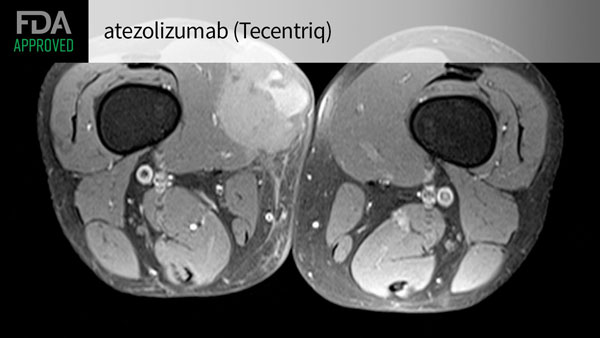

>> Tecentriq(atezolizumab)

近日,美國(guó)FDA批準(zhǔn)Tecentriq(atezolizumab)新適應(yīng)癥,用于治療2歲及以上患有不可切除或轉(zhuǎn)移性ASPS患者。

Tecentriq是一種PD-L1單克隆抗體,通過(guò)與腫瘤細(xì)胞和腫瘤浸潤(rùn)免疫細(xì)胞上表達(dá)的PD-L1結(jié)合,阻斷其與PD-1和B7.1受體的相互作用。通過(guò)抑制PD-L1,Tecentriq可使T細(xì)胞重新激活。

此次批準(zhǔn)基于一項(xiàng)II期研究的數(shù)據(jù)。

共入組49名患者,評(píng)詁了Tecentriq的療效和安全性。

成人患者劑量為每2周840mg,每3周1200mg,或每4周1680mg,直至疾病進(jìn)展或出現(xiàn)不可接受的毒性。

兒童患者的推薦劑量為每3周15mg/kg(最多1200mg),直至疾病進(jìn)展或出現(xiàn)不可接受的毒性。

研究的主要終點(diǎn)為總緩解率(ORR)和緩解持續(xù)時(shí)間(DoR)。

結(jié)果顯示:

1、患者的總體ORR為24%,在出現(xiàn)客觀緩解的12名患者中,67%的患者DoR≥6個(gè)月,42%的患者DoR≥12個(gè)月。

2、最常見(jiàn)不良反應(yīng)為肌肉骨骼疼痛、疲乏、皮疹、咳嗽、惡心、頭痛等。

“鑒于ASPS的轉(zhuǎn)移率高,長(zhǎng)期預(yù)后差,而傳統(tǒng)療法療效欠佳,存在巨大的未滿足臨床需求。Tecentriq在試驗(yàn)中展現(xiàn)出的臨床活性,有望為這類(lèi)患者帶來(lái)新的希望?!?/p>